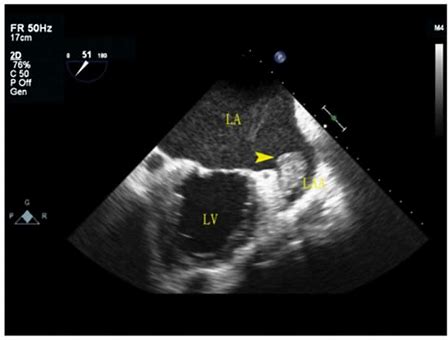

What cardiac condition is demonstrated in this image?

LA appendage thrombus